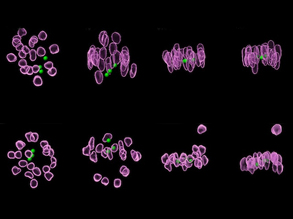

Developing Organoid Screen